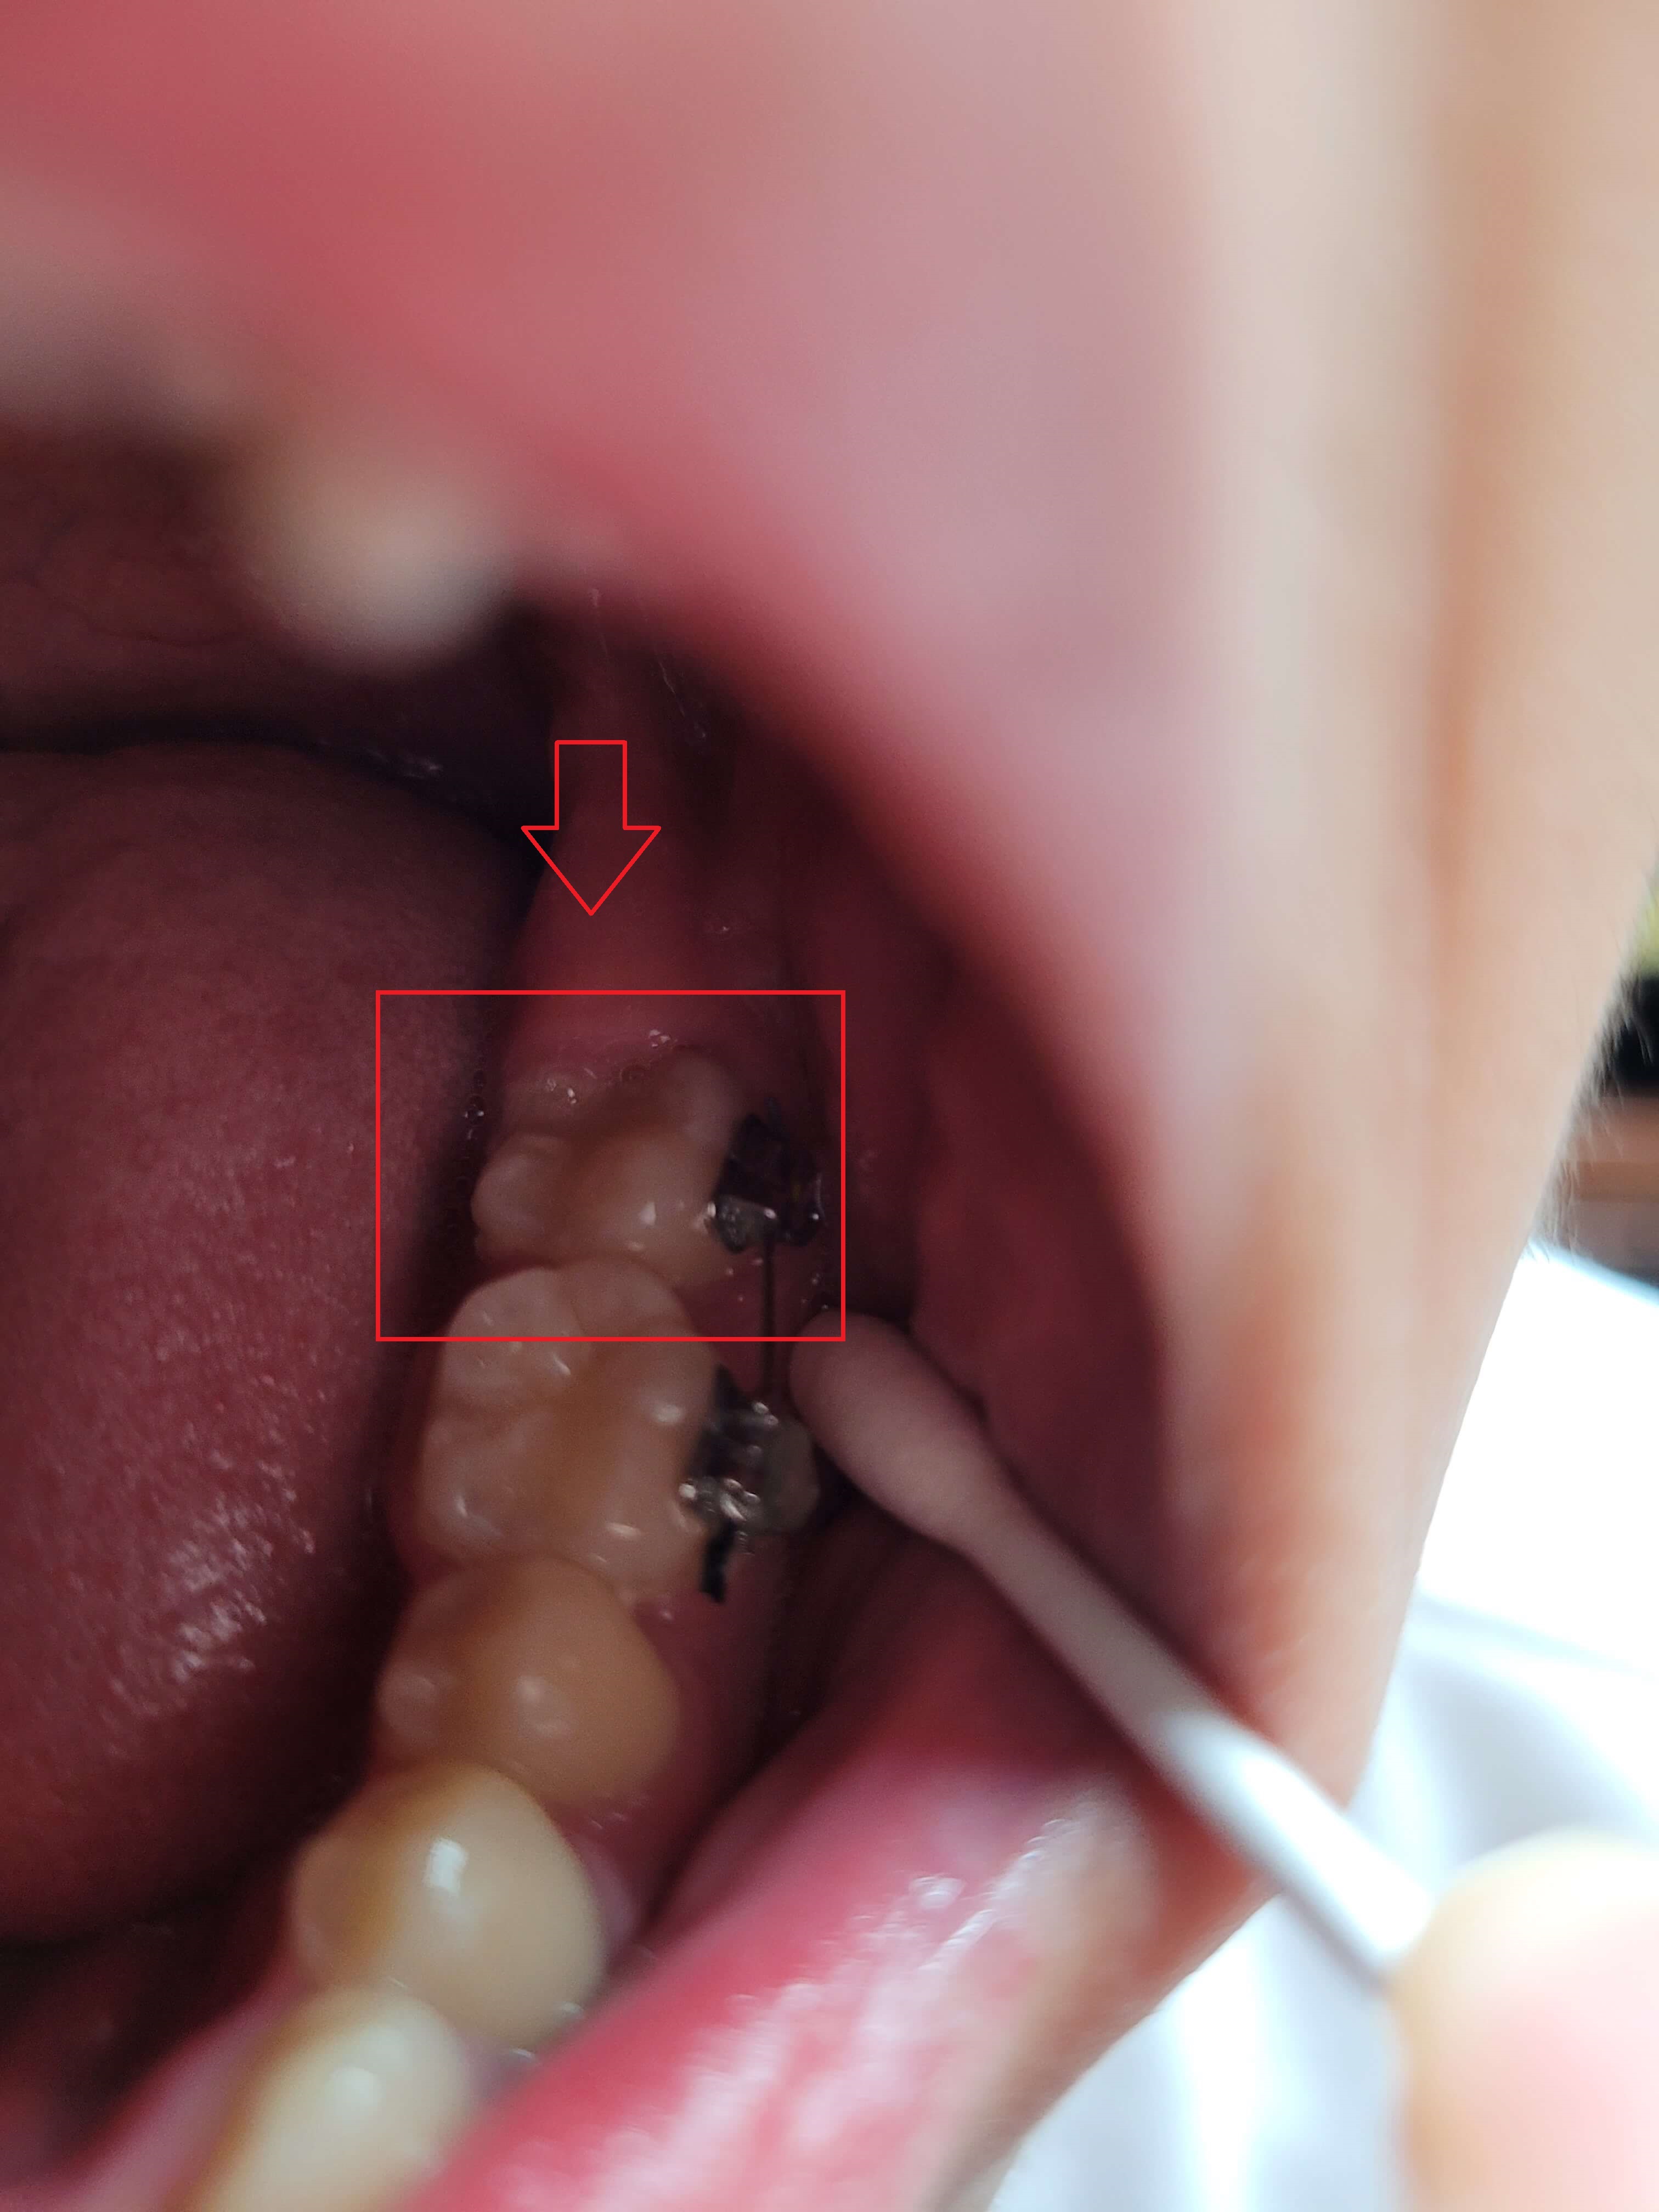

2. 가위교합 교정실시 (3개월 상태)

사진을 보시면 거의 정상으로 돌아왔습니다. 사실 이때 이 정도면 그냥 살아도 되지 않나 하는 생각도 해보았습니다.

하지만 이 상태로 두면 치아는 복원력이 강해 다시 누울 수 있고 어금니가 일어섬으로써 다른 치아들과 맞물리는 높이가 맞지 않아 더 큰 문제 발생된다는 것을 알았습니다.

윗 어금니는 생각보다 제자리에 돌아오는 속도가 늦었으나 전체 블라켓을 설치하고 과개교합 교정에 들어갔습니다.

▼ 3개월 후 어금니 가위교합 교정상태(아래 어금니)

▼ 3개월후 어금니 가위교합 교정상태(윗 어금니)